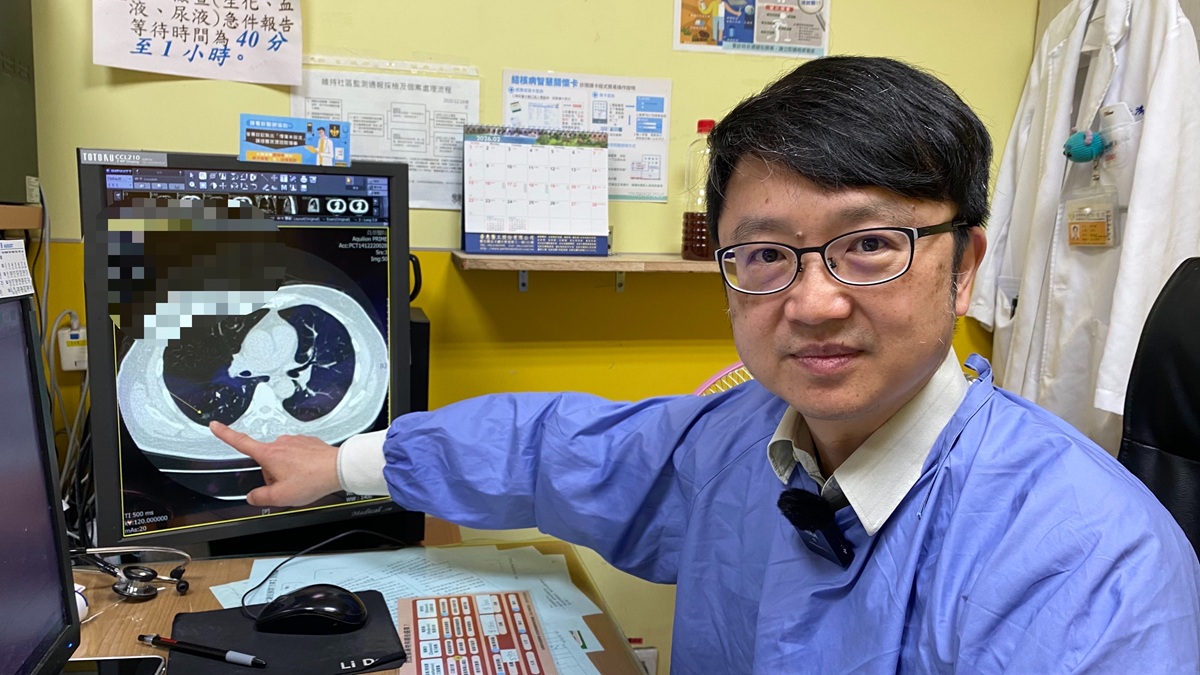

▲林鴻慶主任指出,肺癌早期症狀往往不明顯,容易被忽視,導致延誤就醫時機。(圖/員榮醫院提供)

▲林鴻慶主任指出,肺癌早期症狀往往不明顯,容易被忽視,導致延誤就醫時機。(圖/員榮醫院提供)

林鴻慶主任指出,肺癌早期症狀往往不明顯,初期可能僅出現輕微咳嗽、疲倦或呼吸不適等非特異性表現,容易被忽視,導致延誤就醫時機。臨床統計顯示,超過一半患者確診時已屬中晚期,錯失黃金治療期,不僅治療難度提高,預後與存活率也相對不理想。